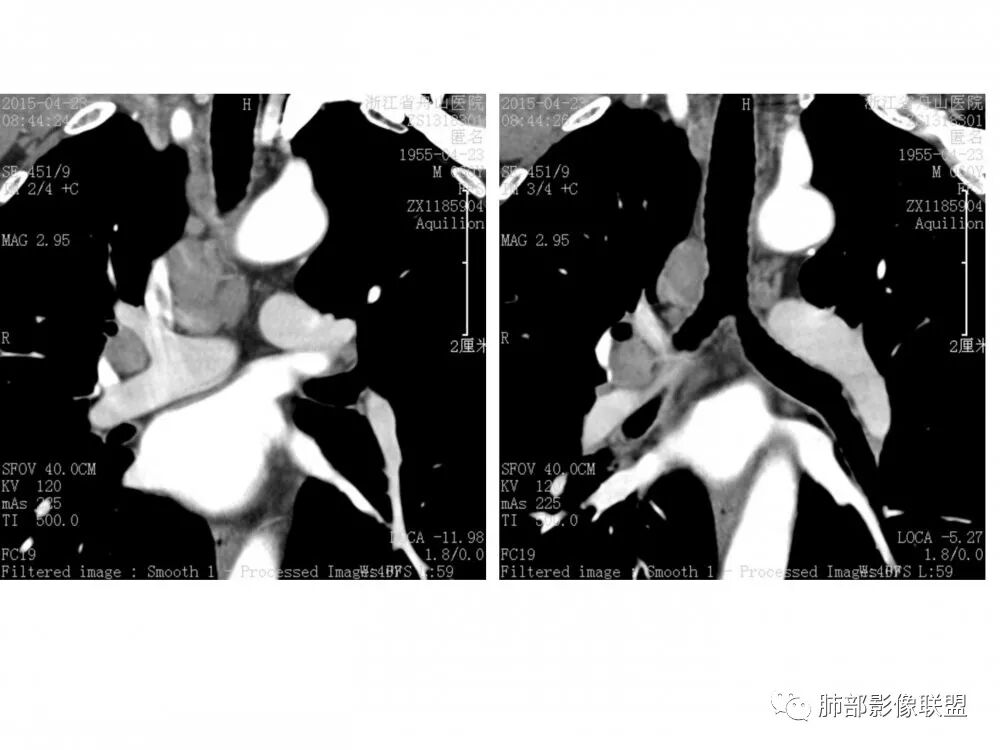

右肺下叶支气管开口新生物,轴位管腔及纵向基底干大部分受累狭窄,支气管管壁破坏明显,强化较低不均匀,肺门、7组、4R淋巴结肿大,考虑恶性支气管腔内肿瘤,鳞癌可能性大,需要与类癌、涎腺类肿瘤鉴别

男,60岁,右肺下叶支气管开口新生物,轴位管腔及纵向基底干大部分受累狭窄,支气管管壁破坏并突破形成腔外肿块,强化较低不均匀,右肺门、7组、4R淋巴结肿大,考虑恶性没问题,鳞癌可能性大,类癌、粘液表皮样癌,乳头状瘤待排。

右肺下叶支气管不规则软组织肿块,病灶沿支气管生长,有一定的张力,部分包绕支气管壁,增强病灶内可见中度强化,内部有延迟强化的特点,周围淋巴结增大,诊断恶性病变无疑,远端无明显支气管阻塞,主要考虑粘液表皮癌,腺样囊腺癌,鳞癌之间鉴别,病灶有类似神经源性病变生长方式,腺样囊腺癌,其次考虑鳞癌或粘液表皮癌。

右肺下叶支气管开口新生物,轴位管腔及纵向基底干大部分受累狭窄,支气管管壁破坏并突破形成腔外肿块,血管累及变细,肉眼观轻度强化,右肺门、纵膈淋巴结肿大,恶性没问题,阻塞性炎症不明显,类癌强化明显不支持,老年男性,首先考虑小细胞癌,鉴别不典型鳞癌和腺癌。

右肺下叶开口支气管内新生物,破坏管壁向腔外膨胀生长,累及各基底段开口,无明显坏死,有局部强化,远端无明显阻塞,右肺门及纵隔淋巴结肿大,考虑恶性肿瘤。大气道肿瘤不支持腺癌。小细胞癌大多为周围病灶引起肺门、纵隔淋巴结转移,肺门淋巴结明显肿大后侵犯支气管粘膜到达支气管内(从外到内),本例病灶从管腔内向腔外长,不支持小细胞癌。病灶为轻→中度强化,类癌显著强化为主→不支持,鳞癌、腺样囊性癌一般中度强化,鳞癌大多有阻塞性病变,本例无明显阻塞不支持鳞癌。粘液表皮样癌一般为轻度不均匀强化。感觉病灶为轻中度不均匀强化。综上首先考虑粘表,其次腺样囊性癌。待支气管镜活检明确。

病理结果:鳞癌